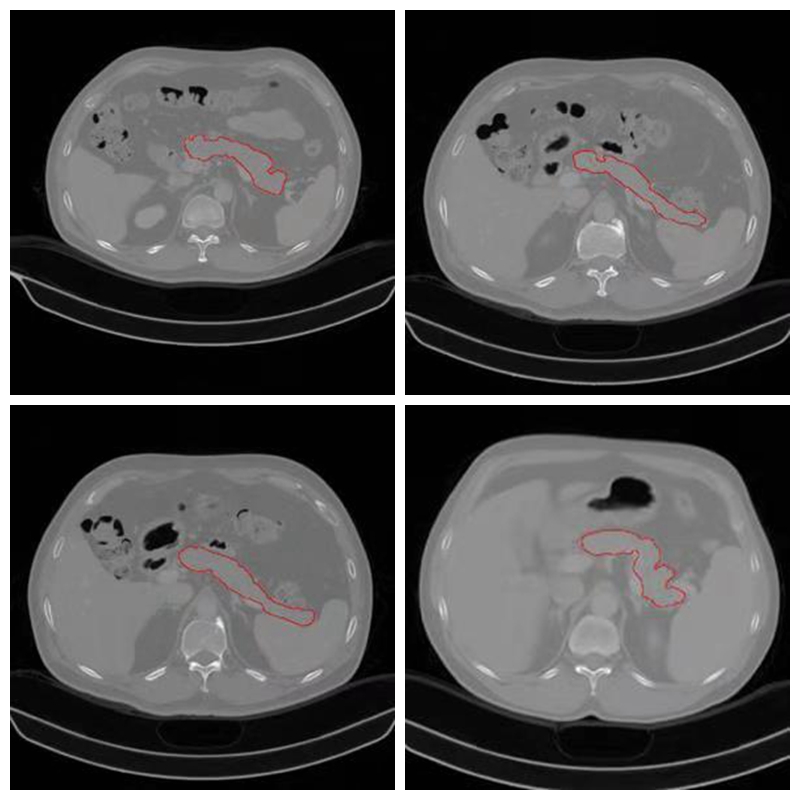

胰腺是人体最重要器官之一,具有内、外分泌功能。近年,胰腺疾病的发病率逐年上升,尤其是胰腺癌,为致死率最高的肿瘤之一,5年生存率小于1%。CT检查为诊断胰腺病变最主要的检查方式,随着数字医疗设备的进步和影像组学和深度学习等领域的发展,利用CT数据进行计算机辅助诊断,准确诊断胰腺病成为可能。而胰腺分割作为计算机辅助诊断基础而重要步骤,研究意义重大。由于胰腺的解剖结构较为复杂,其主要位于后腹膜,形态、位置变异较大,且周围有大量邻近组织,如胃、十二直肠、脾脏及大血管,这些组织在CT图像上与胰腺紧密相连且密度相似,再加上CT图像本身的噪声、局部体效应和组织运动的影响等因素,胰腺分割也是个具有很大挑战性的问题。

此次胰腺CT分割挑战赛,由ISICDM 2018会议组委会联合陆军军医大学数字医学研究所和陆军军医大学西南医院联合主办,旨在通过挑战赛的形式为数字医学产学研界提供技术交流和展示的平台。本项挑战赛收集20例经病理诊断为胰腺癌的病人,40例正常对照组(男性、女性各20例)。扫描设备为西门子64排CT(Definition AS, Siemens),扫描方案为标准胰腺扫描方案,受试者仰卧位躺于扫描床上,扫描范围上包括膈肌,下包括坐骨结节。共采集平扫、动脉期、静脉期三组数据。平扫完成后依据体重经肘静脉推注非离子造剂(欧乃派克350 GE)100-120ml,注射速度为4-5ml/s,注射完成后25-30s采集动脉期,60s采集静脉期。扫描参数为管电压120KV,有效管电流为60-110mAs,准直宽度为16x1.2mm,螺距为0.8,分别行1mm和5mm重建。因胰腺分割在临床上多采用静脉期,所以本次挑战赛仅选取了静脉期图像。